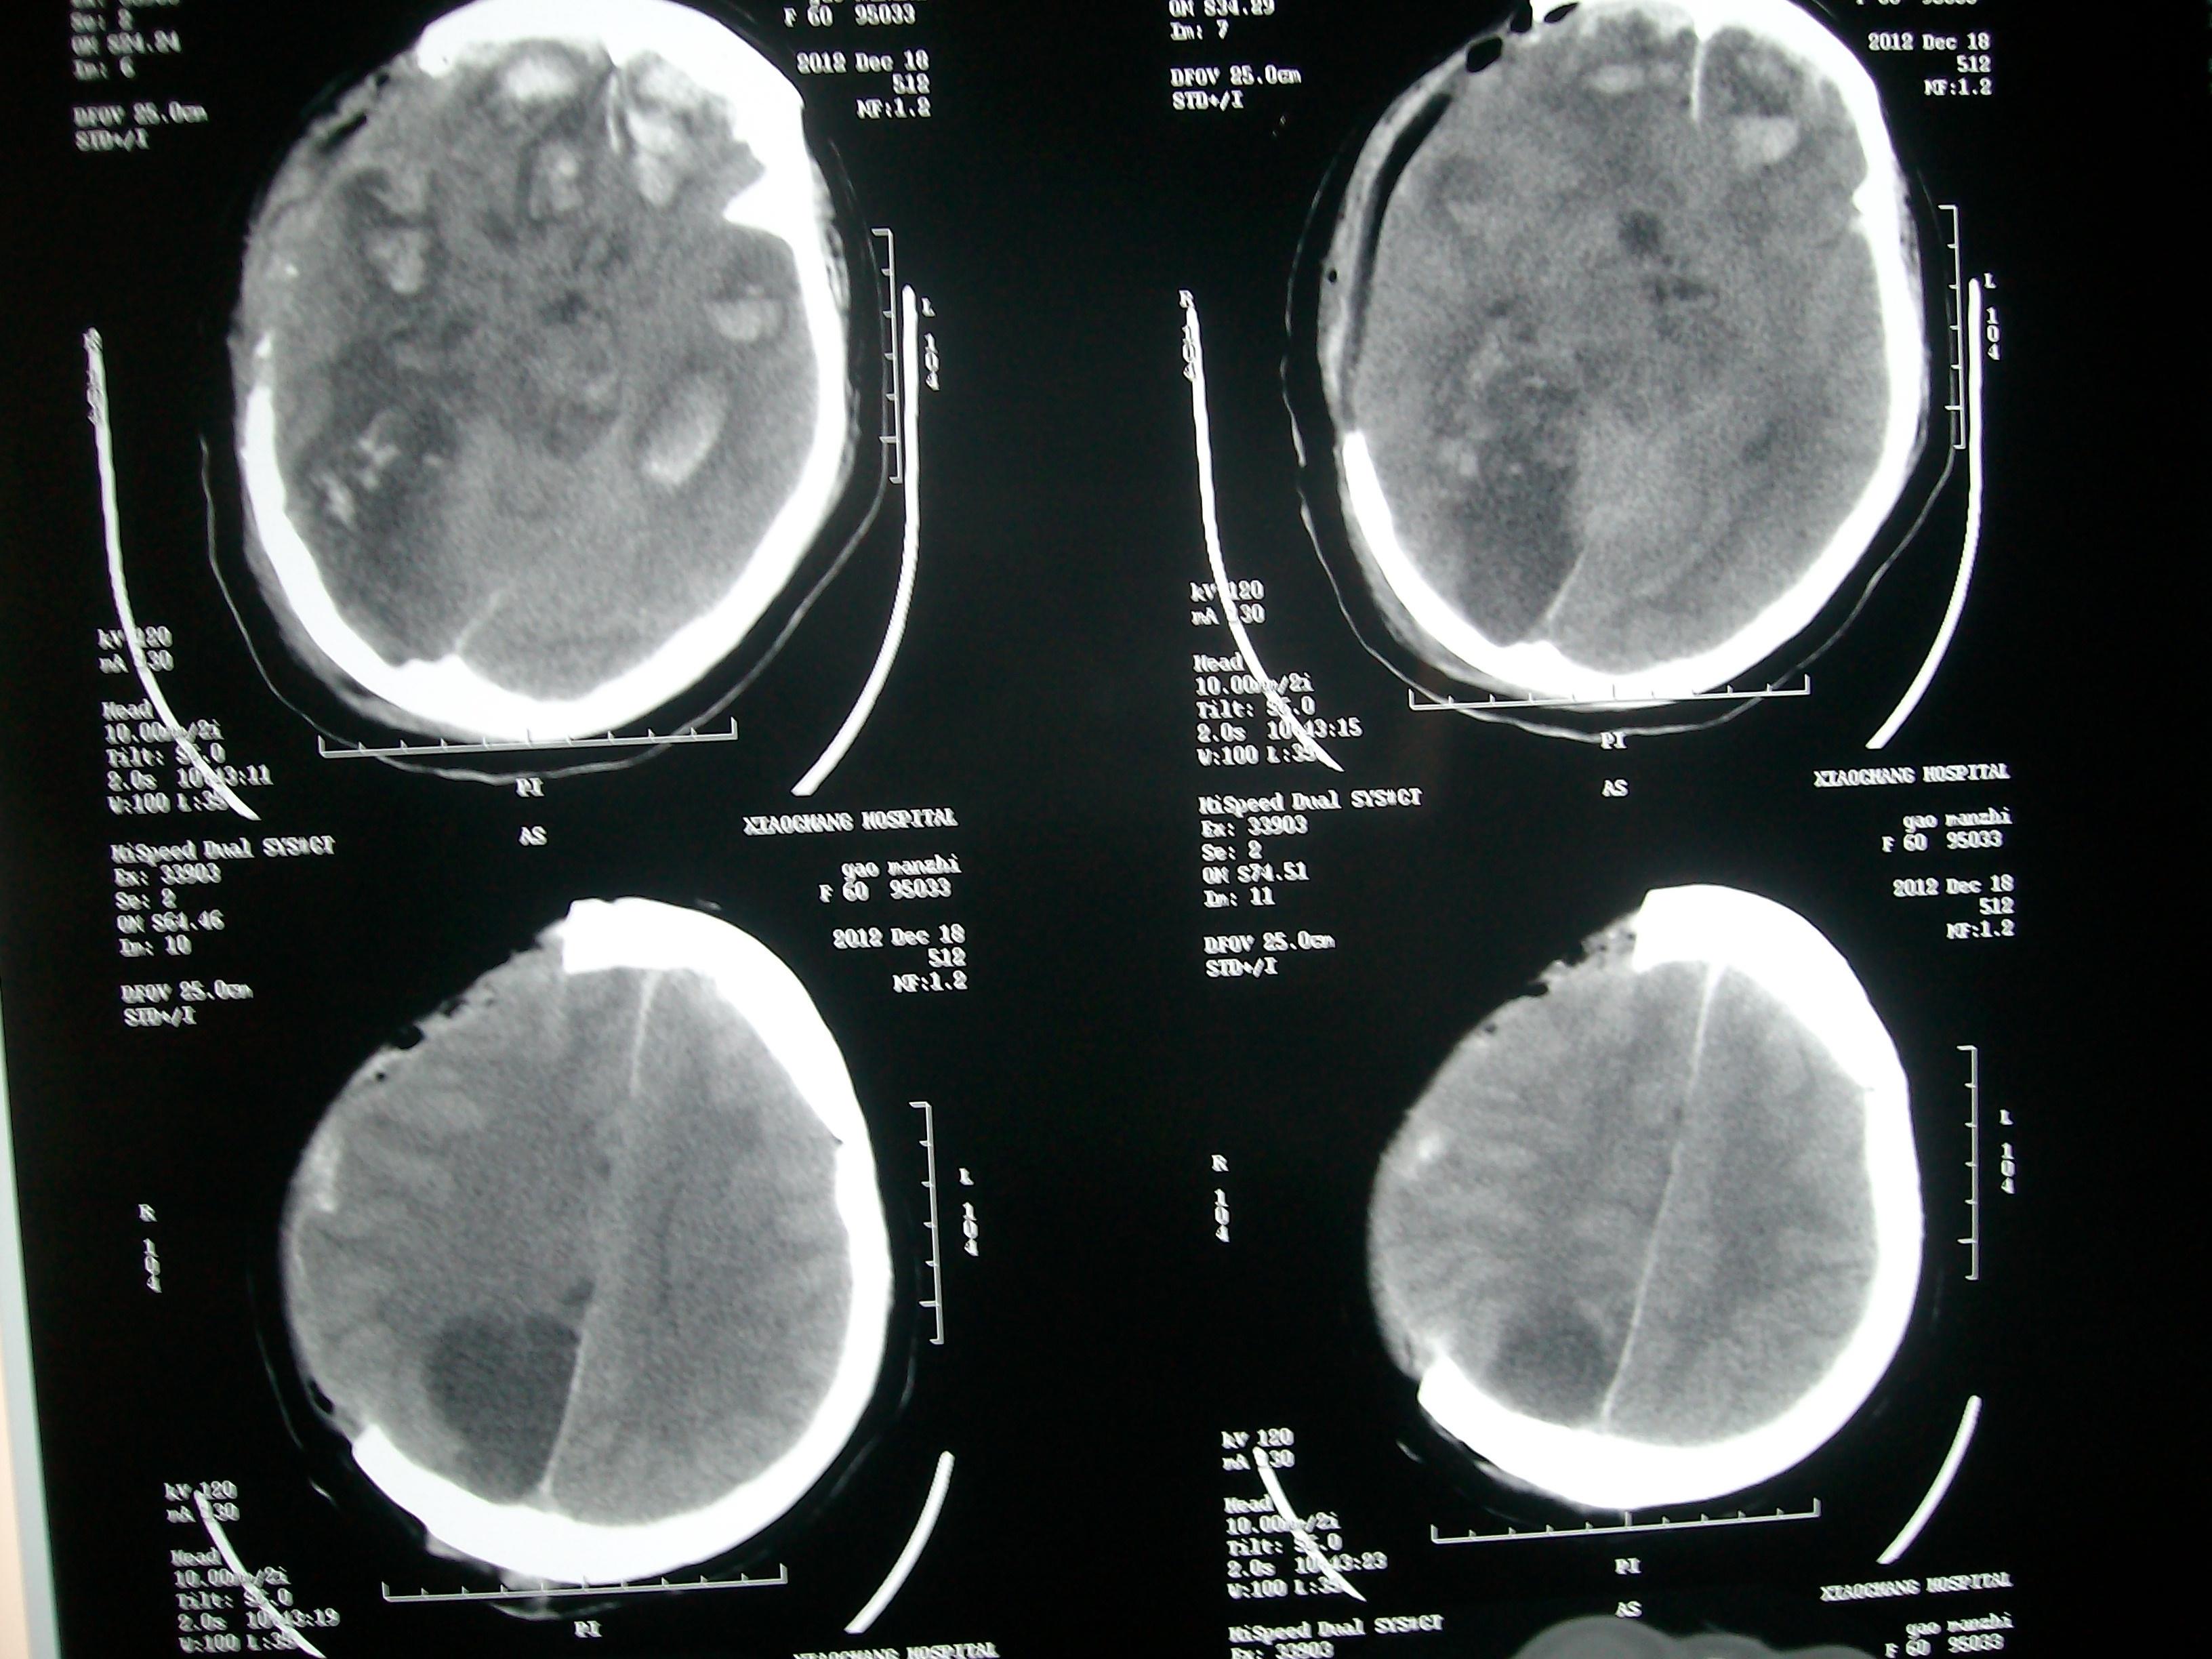

【读片】急诊外伤头部ct,请会诊! [病例帖]

发病18小时后手术.术后症状有加重,于术后第二天复查ct

薛开喜今年82岁,站在凳子上约60厘米摔下来了,在水泥地上,右后脑着地